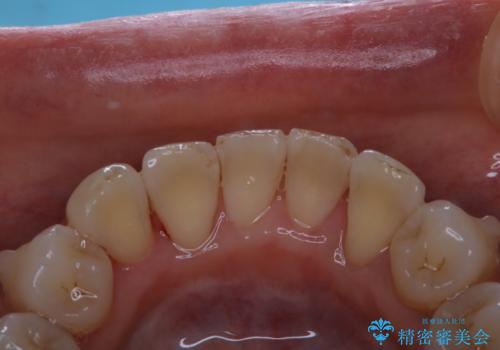

マウスピース矯正中にPMTC

- マウスピース矯正中のため、口臭や虫歯予防をしっかりとしたいとのことでした。PMTC30分コースを行いました。

矯正治療中は虫歯や歯周病リスクが高くなることがあります。

インビザライン矯正治療はマウスピースを長時間使用するため、歯石や汚れ・着色などが付着したままだと、フィットが悪くなったり、口臭が強く出たりする原因につながることもあります。

定期的にPMTCを行うことをおすすめします。